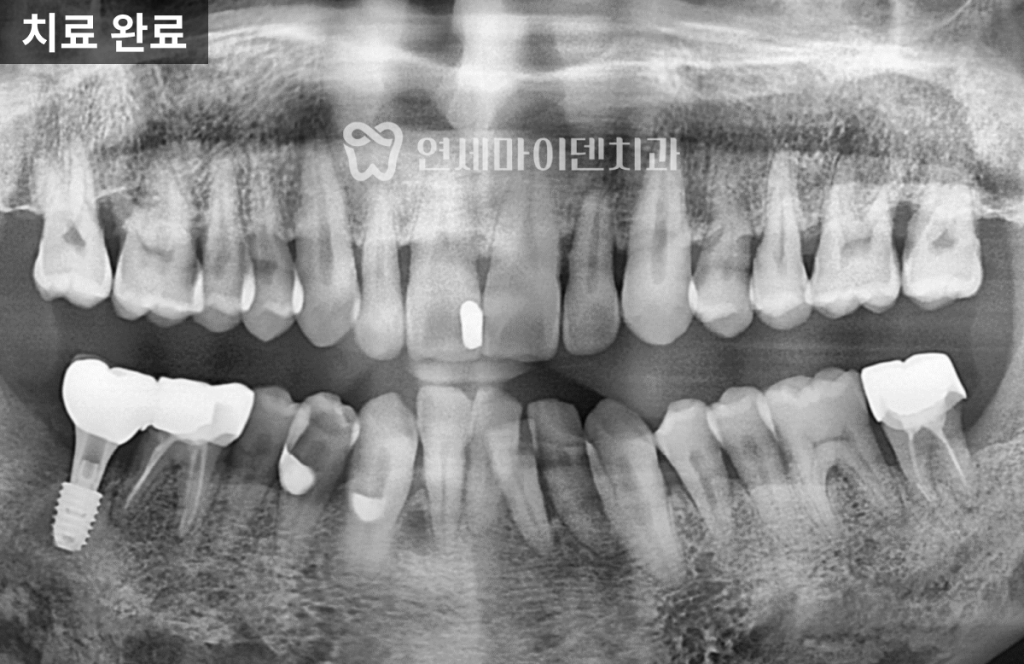

4년 경과: 결과는?

이번 케이스는

4년이 지난 현재까지✔ 임플란트 안정적 유지

✔ 주변 치아 뼈 레벨 유지

✔ 정기 관리 지속임플란트의 수명은